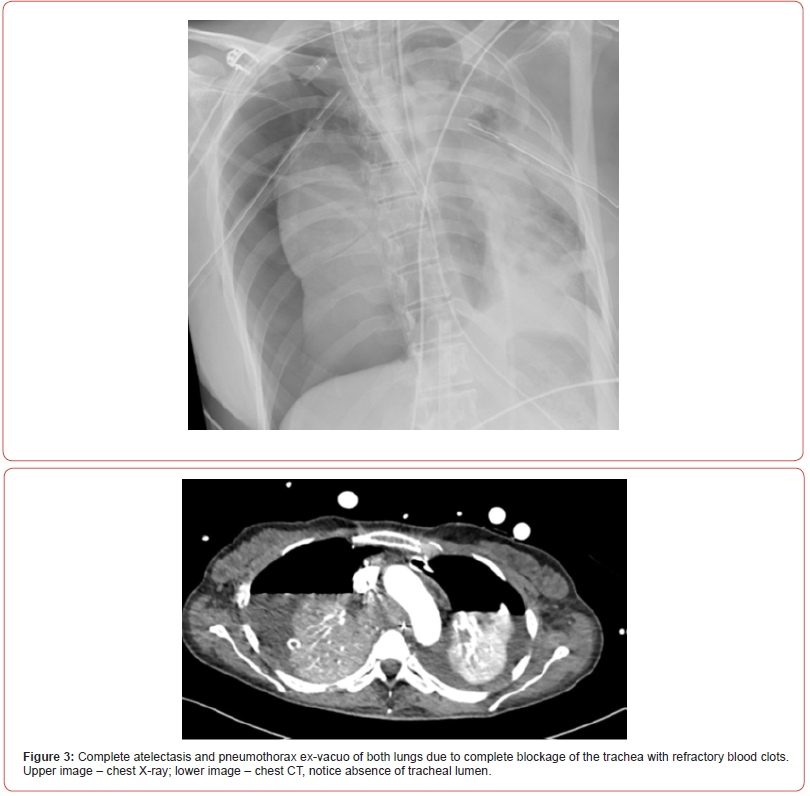

Shortly after, the situation escalated rapidly; the patient experienced a sudden desaturation to 70% and was emergently intubated. Mobile chest x-ray revealed complete atelectasis of the left lung (figure 1). Immediate bronchoscopy showed large amount of blood and blood clots in the left main bronchus and despite ongoing suctioning, the left lung did not re-inflate and the patient remained severely hypoxic. Few hours later a venous-venous extra-corporal membrane oxygenation (VV-ECMO) was emergently placed due to refractory hypoxemia (figure 2). In the following days, the patient’s lungs did not re-inflate despite multiple bronchoscopies performed due to ongoing bleeding that filled the airways with blood clots up to the upper trachea (figure 3). Tracheostomy was placed but blood clots filled also the tracheostomy tube that needed to be capped to prevent ongoing blood loss. The patient was treated with full VV-ECMO support, disconnected from the ventilator due to zero tidal volume secondary to the blocked trachea, and in the following weeks developed septic shock and acute renal failure requiring hemodialysis. In attempt to stop the ongoing bronchial bleeding the patient was transferred almost daily to the radiation oncology unit to receive radiation while on VV-ECMO (20 Gy in 10 fractions over 2 weeks) to the proximal tracheobronchial tree [4]. During and after completion of the radiation, multiple bronchoscopies aimed at controlling bronchial bleeding and clearing airway obstructions were conducted, unfortunately unsuccessfully.